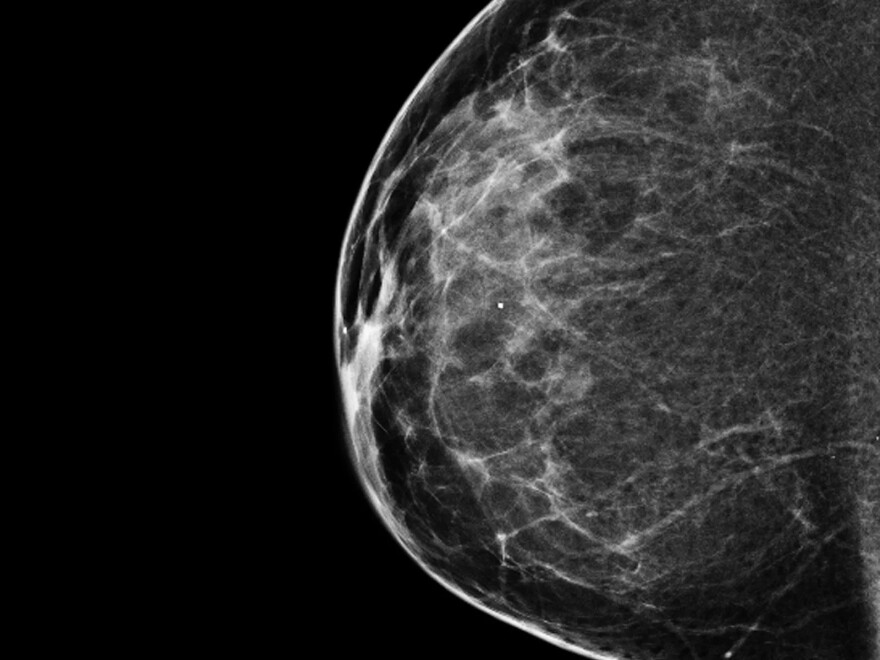

A 3-D mammogram reveals a normal breast